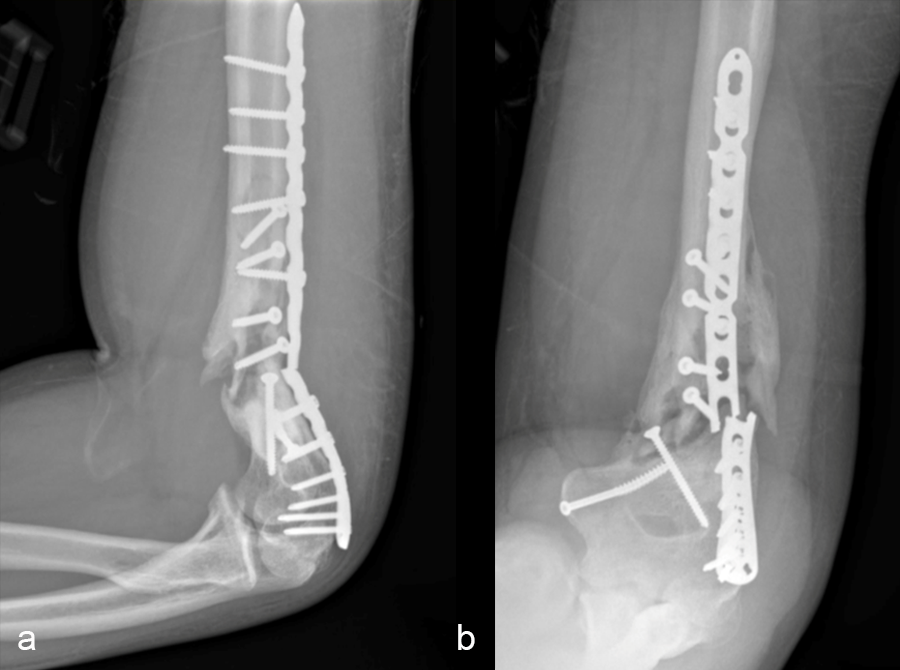

In a first stage, the distal humerus was debrided and devitalized bone was resected, leaving an 8cm defect into which a cement spacer was placed. New plates were inserted to stabilize the fracture (Fig 17 and Fig 18). Cultures taken in the OR were negative.

In October 2022, planning began for the second stage of surgery. A graft cage was planned (Fig 19) to allow the formation of new bone in the 8cm defect.